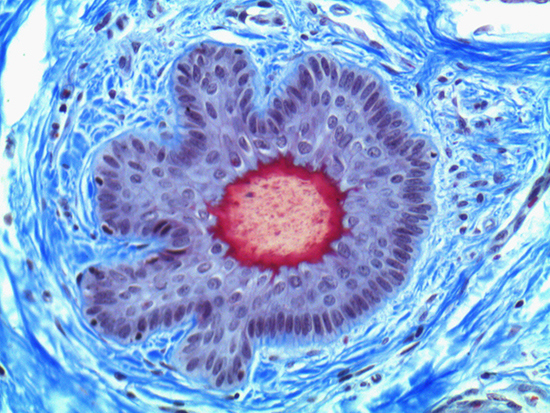

Masson's trichrome stain is incredibly effective in differentiating cells and their components from the surrounding connective tissues. One of the most common stain types, which has been used on the dermal tissue sample seen in the images within this article, yields a number of colors where cell nuclei appear dark red, collagen and other tissues appear green or blue, and cell cytoplasm appear red/purple (Jones, 2010). These stains have been imaged under brightfield and darkfield illumination, and then again with specific filters to selectively focus on the cellular constituents of the epidermis. The primary application for the epidermal trichrome stains is differentiating healthy collagen and muscles from connective tissues onset with tumorigenesis. Typically the tumors proliferate from muscle cells and fibroblasts deep in the dermal tissue (Blitterswijk, 2010).

Figure 1: Brightfield Image of Dermal Tissue

When comparing Figures 1 and 2, the visual differences are significant. A brightfield image is formed with the illumination source below the sample, and then transmitted light propagates through the sample to the sensor forming a bright, white background with sharp color. A darkfield image is formed by directing light at an oblique angle through the sample, forming a hollow cone of light which is collected by the objective. Darkfield illumination typically yields a dark background with sharp color, but in the case of Figure 2, the collagen and muscle fibers interfered with the light path and caused a blur of light and color. The dark background is hardly evident and only two distinct colors are visible. When analyzing histological stains, brightfield illumination is the preferred technique for lighting a sample.